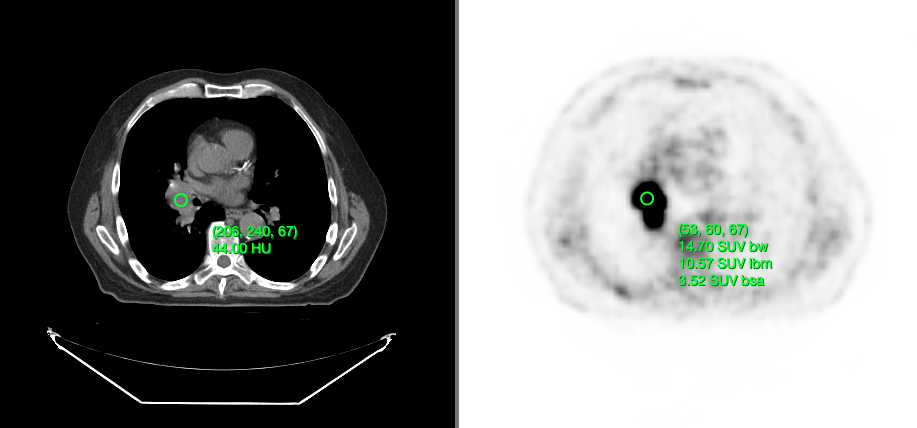

Below, you can see a screenshot of the annotation tools that are available in Cornerstone3DTools.

Cornerstone3DTools is capable of calculating dynamic statistics based on the modality of the volume being rendered. For instance, for CT volumes a ProbeTool will give Hounsfield Units and for PET it will calculate SUV stats.